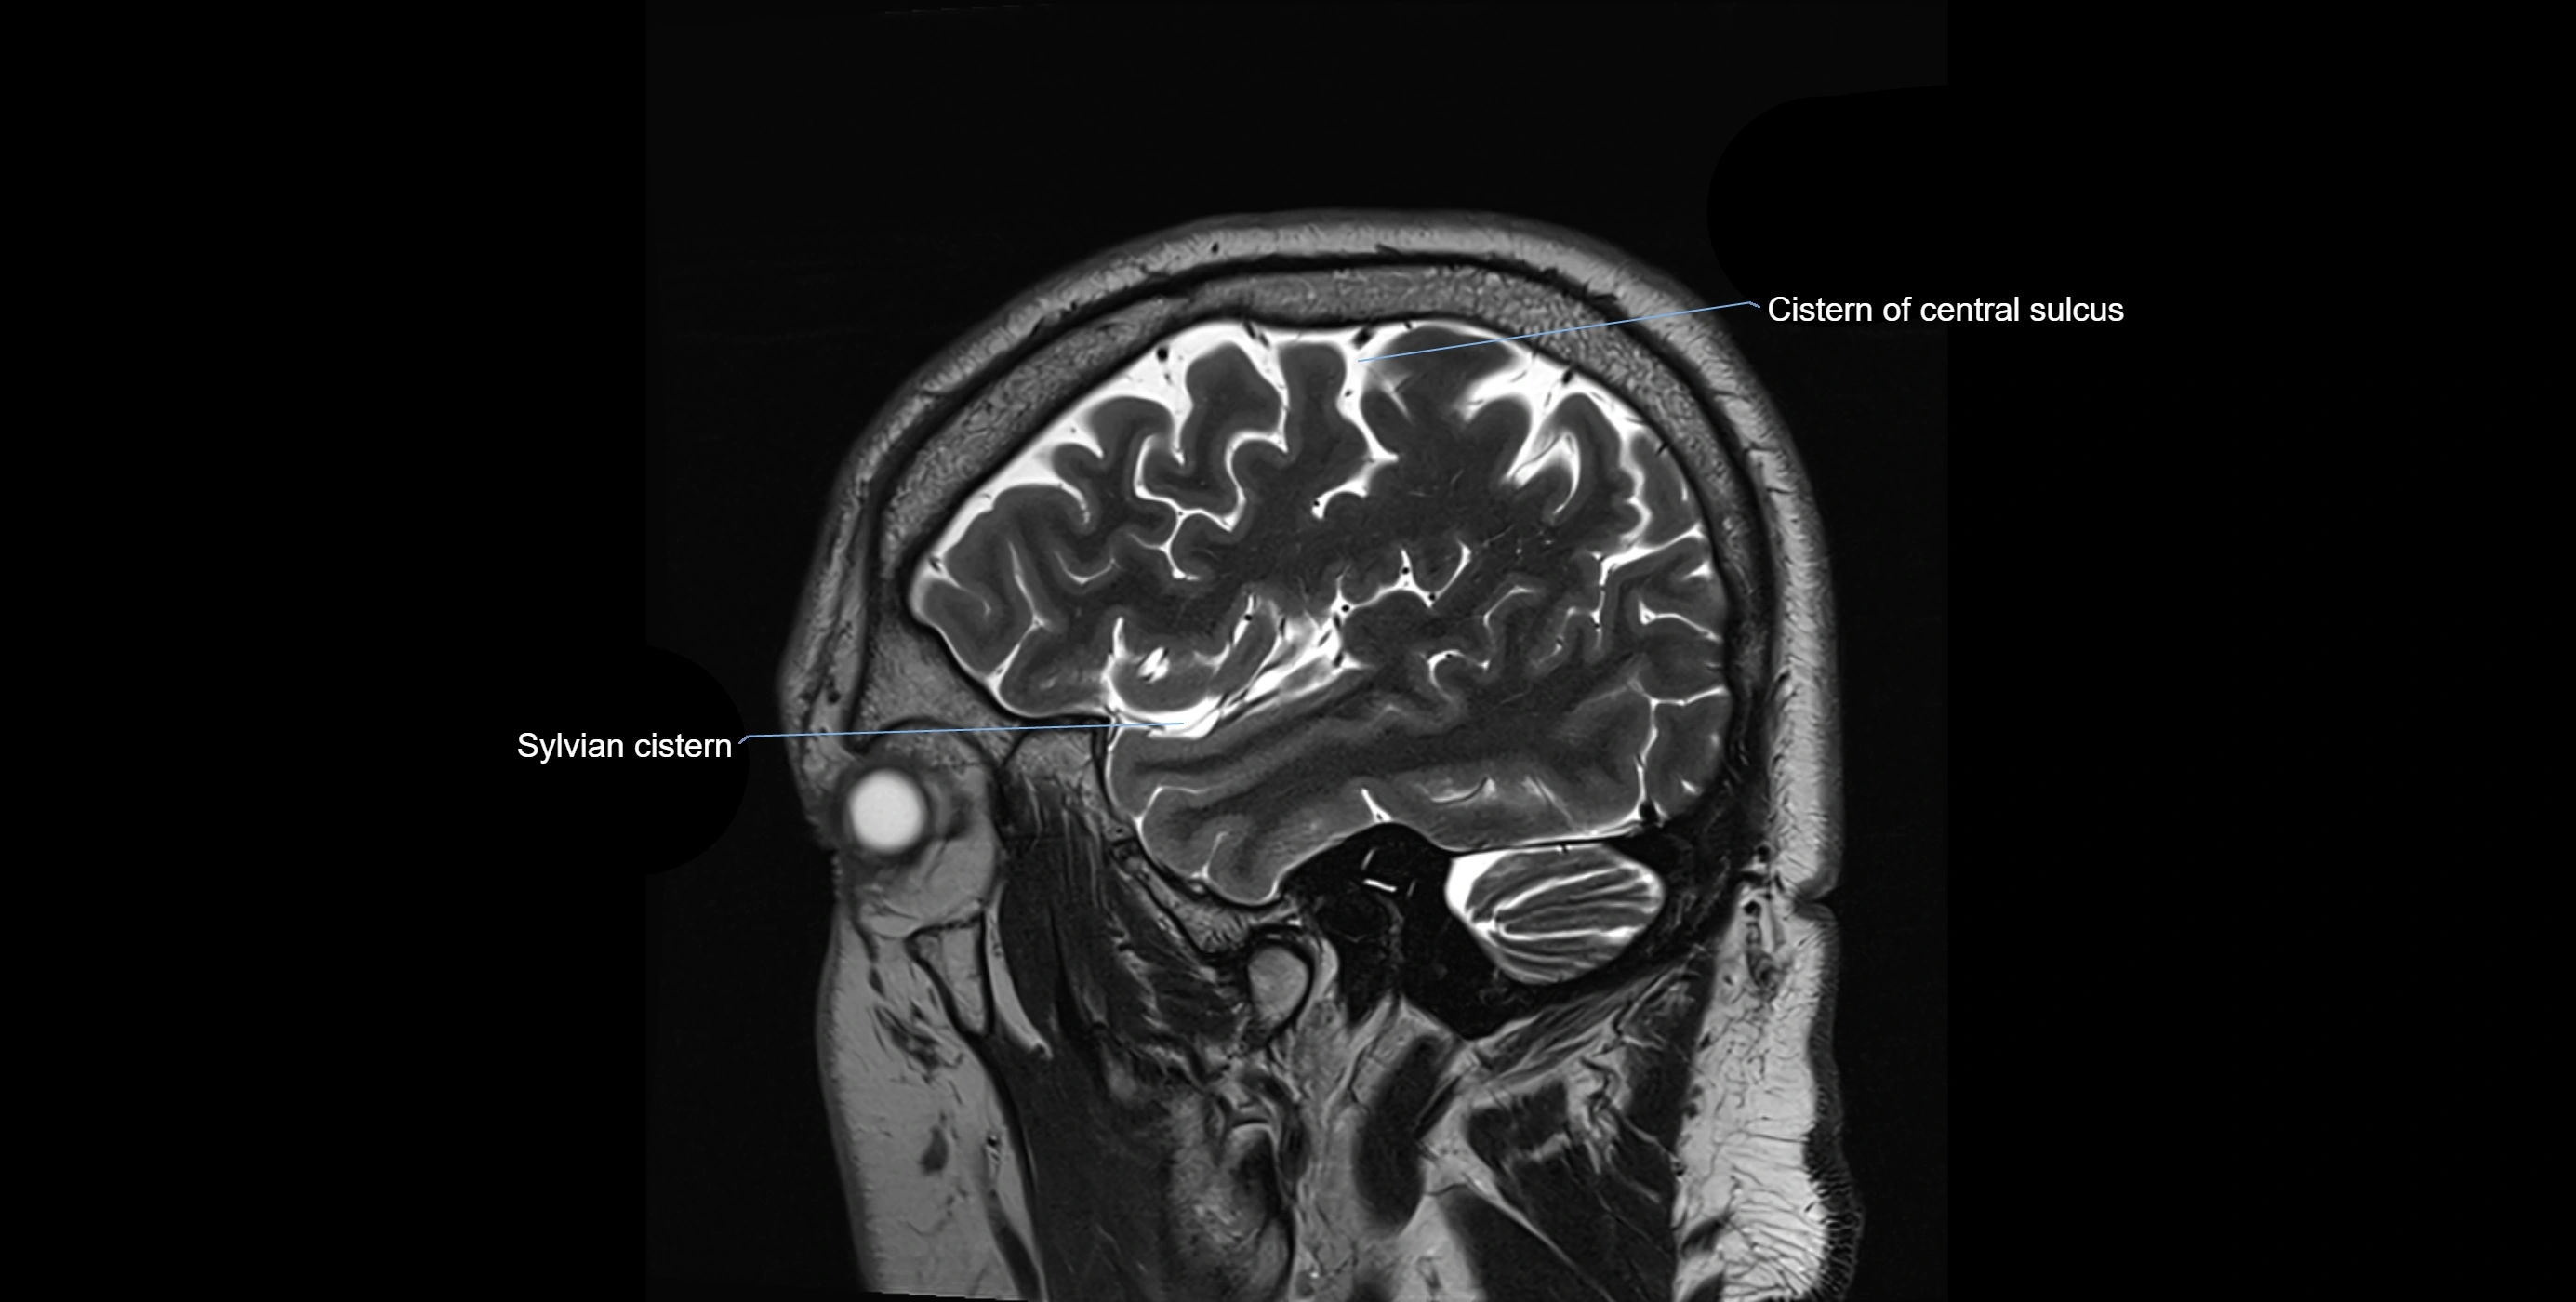

MRI images

image